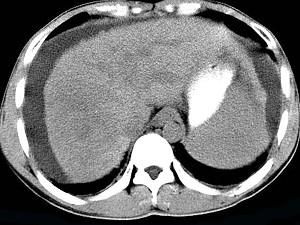

问题 男,35岁,有乙肝病史多年,AFP阳性,影像检查如图,最可能的诊断是 ( )

选项 A、肝癌、硬化腹水 B、肝硬化、结节性增生 C、肝血管 D、肝脓肿 E、肝硬化腹水

答案 A